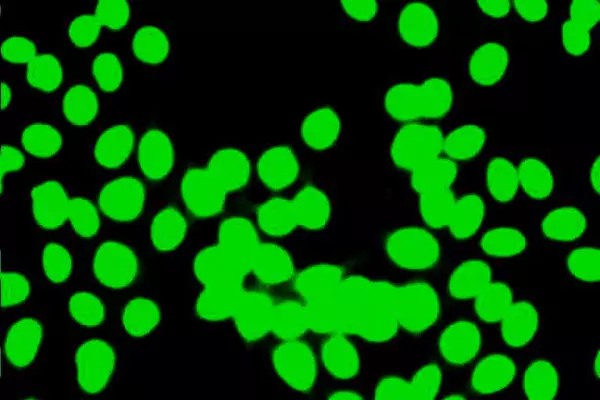

Add to cartANA By IF With Titer

ANA By IF With Titer